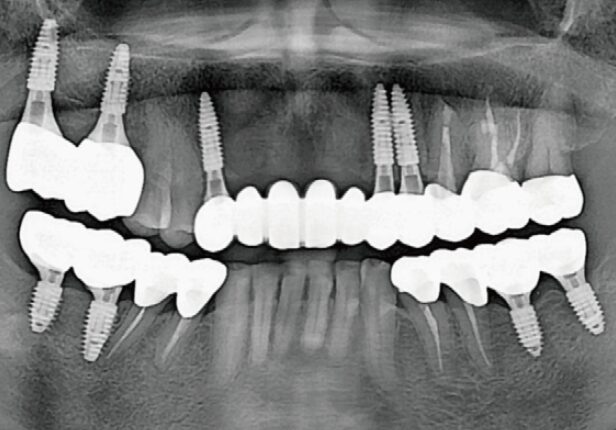

Pre-surgery panorama

Post-surgery panorama

Final Crown Panorama